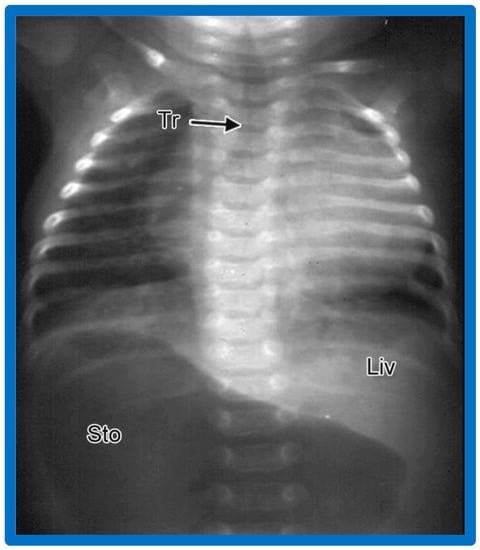

3.9. Isolated Dextrocardia

Isolated dextrocardia is a phrase used to characterize subjects with dextrocardia, but the viscera are normal in position (situs solitus), i.e., dextrocardia with situs solitus (Figure 3 and Figure 10).

Figure 10. A chest roentgenogram of a baby illustrating dextrocardia along with normal visceral position (situs solitus) with the liver (Liv) on the right side and the stomach (Sto) on the left side, i.e., isolated dextrocardia. The tracheal (Tr) position in the middle is shown. The Sto is dilated, probably related to intestinal obstruction secondary to malrotation of the gut. Modified from reference [4].